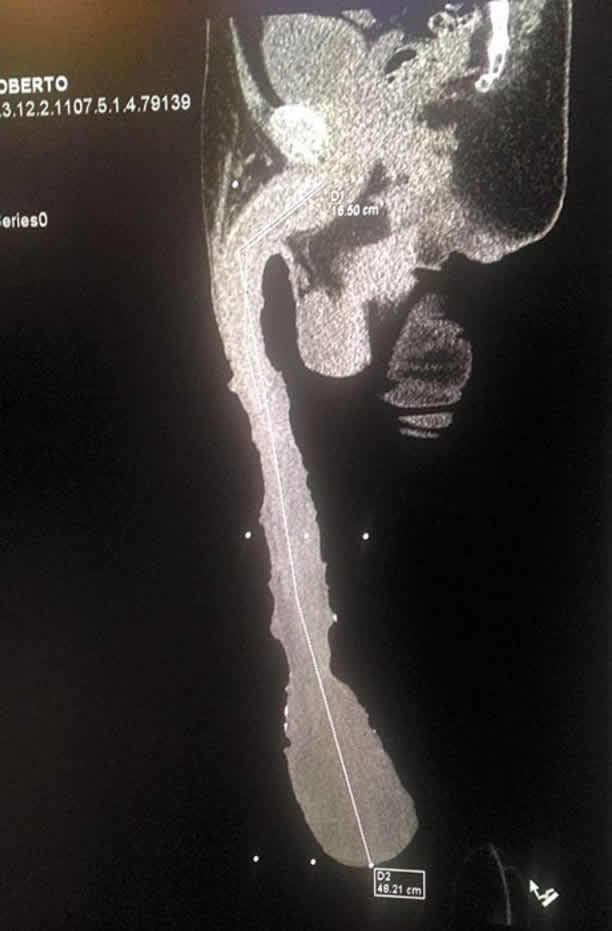

El saltillense Roberto Esquivel Cabrera tiene un pene de 48.2 cm y por ello es tratado en un Centro de Salud donde están investigando por qué esta parte de su anatomía se desarrolló tanto. A Roberto lo apodan “Centauro”…